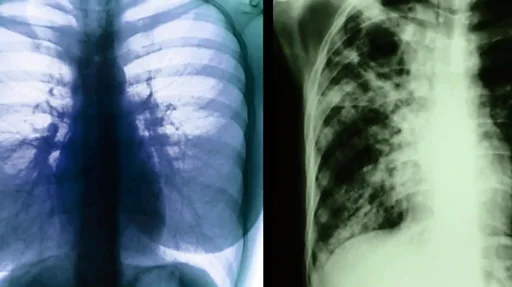

எக்ஸ்ரேவைக்கொண்டு காசநோயை கண்டறிய முடிந்ததன் விளைவாக ஆயிரத்து தொள்ளாயிரத்து எழுபதுகளில் பிரிட்டனில் காசநோய் பாதிப்பு பெருமளவு சரிந்தது.